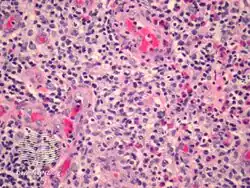

Epithelioid haemangioma is a non-cancerous tumor typically found in skin and soft tissue of usually the head and neck region, where it presents with reddish-pink itchy painful bumps.[1] It can occur in bone as a type of vascular tumor of bone, where it can give rise to pain and swelling.[2]

It is made up of well-formed blood vessels lined by lymphocytes and eosinophils (types of white blood cells).[1]

Angiolymphoid hyperplasia with eosinophilia/pathology